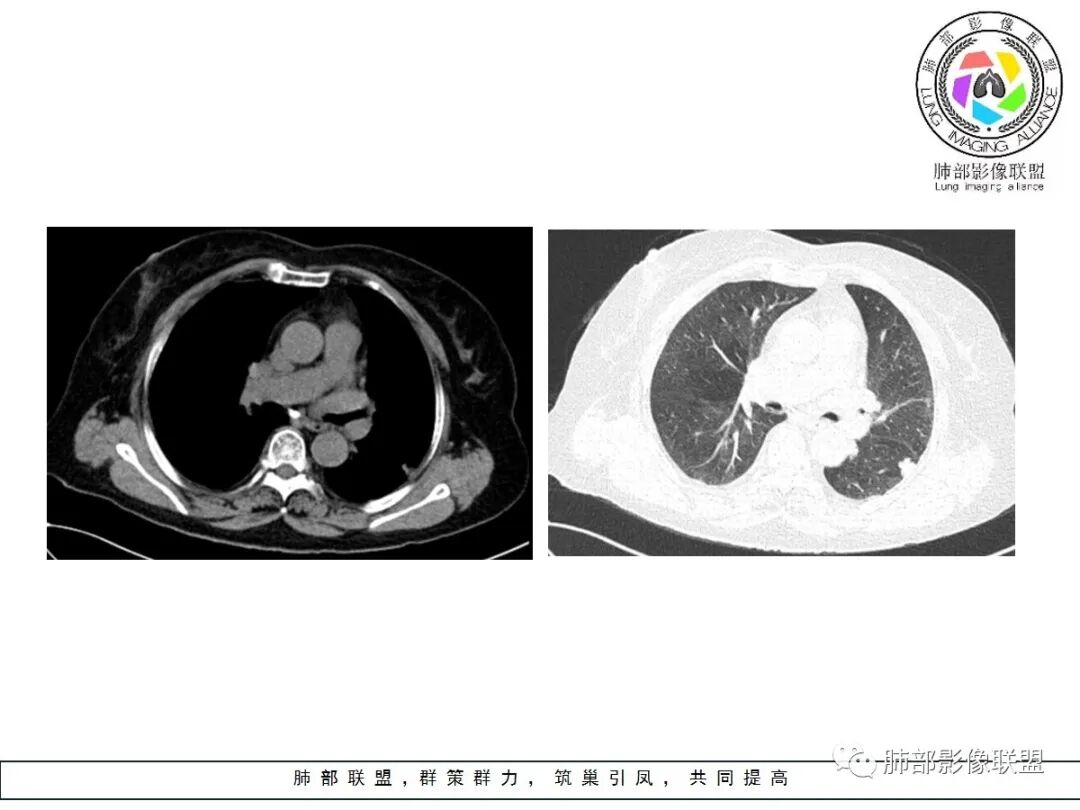

良性征象(宽基底与胸膜相连,没有明显胸膜凹陷与微积液,收缩力较弱,仅仅叶间胸膜略凹陷,边缘平直,U形凹陷为主,结节较散,增强动脉期强化太明显)>恶性征象(局部略有膨隆,叶间胸膜略凹陷),可疑征象(图像不太好,支气管截断不确定,分叶征象不确定,也可能是散在结节的假象,脐凹征可疑),综合考虑良性结节可能大(隐球?结核?其他炎性结节?局部肺栓塞?)腺癌待排,临床简单,穿刺一下就OK。

左肺下叶胸膜下结节,边缘部分平直收缩部分膨隆,可疑脐凹征,邻近叶间裂稍牵拉,胸膜糊墙,增强扫描均匀强化,老年女性,良恶性征象都有,平扫密度似略偏高,先考虑良性,隐球菌?一般炎性肉芽肿?腺癌待排,老年人,警惕性提高一个级别,治疗后复查或穿刺活检。

左肺下叶前基底段斑片状影,边界清楚,增强强化15Hu,冠状位矢状位,边缘平直,胸膜下胸膜外脂肪间隙尚清楚,轻度强化,先抗炎,三个月复查。

有胸膜牵拉,老年女性,角蛋白19片段稍高,部分层面稍膨隆,呈球形,边界太清楚,恶性待排除,先抗炎,三个月复查。